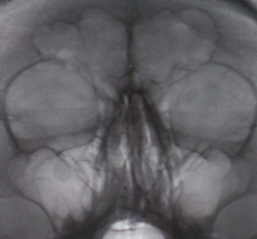

На снимках регистрируется окаймляющая стенки пазухи плотная тень шириной от 0,3 до 0,5 см и более, которая отлича­eтcя от таковой при остром процессе не только шириной, но и стойкостью. При динамическом наблюдении эта тень не исчезает – иллюстрации 8 и 9.

На иллюстрации 8. Определяется снижение прозрачности лобной пазухи довольно однородной структуры с локальным утолщением её над правой орбитой. Справа определяется пристеночное снижение прозрачности гайморовой полости с не четким и неровным контуром, особенно базально. Слева определяется субтотальное снижение прозрачности, с выраженным пристеночным снижение прозрачности вдоль верхней стенки.